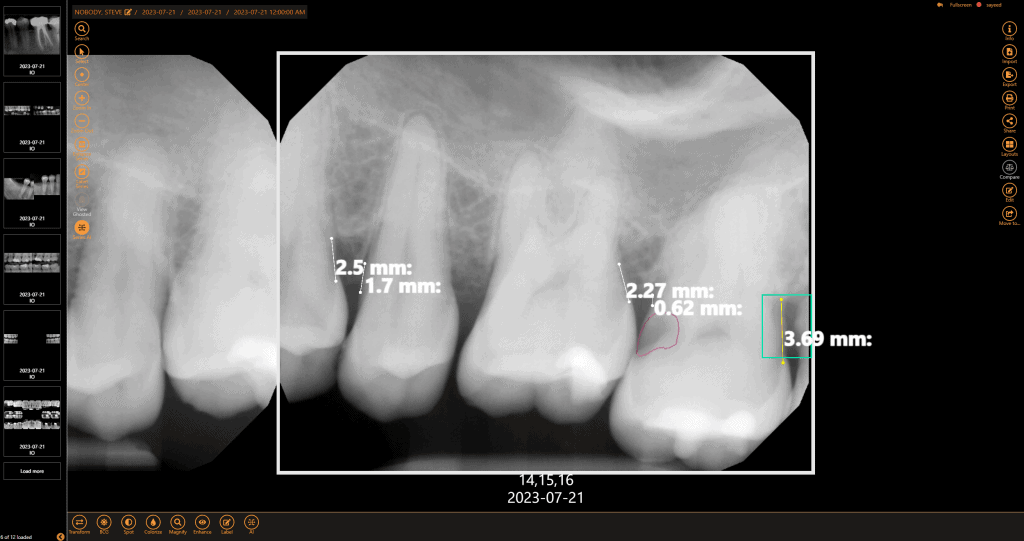

Get a second opinion to quickly detect decay, identify tartar buildup, and assess bone levels, ensuring a more accurate diagnosis of periodontal disease.

Speed up diagnosis and treatment planning with fast initial screenings and real-time AI feedback, giving you confidence in chairside decisions.

Within minutes, have more data than ever to guide and support your diagnosis with the patient chairside. AI makes it easier to visualize the areas of concern so patients can make a more informed decision.

Submit claims with greater confidence when the diagnosis is supported by quantified data.